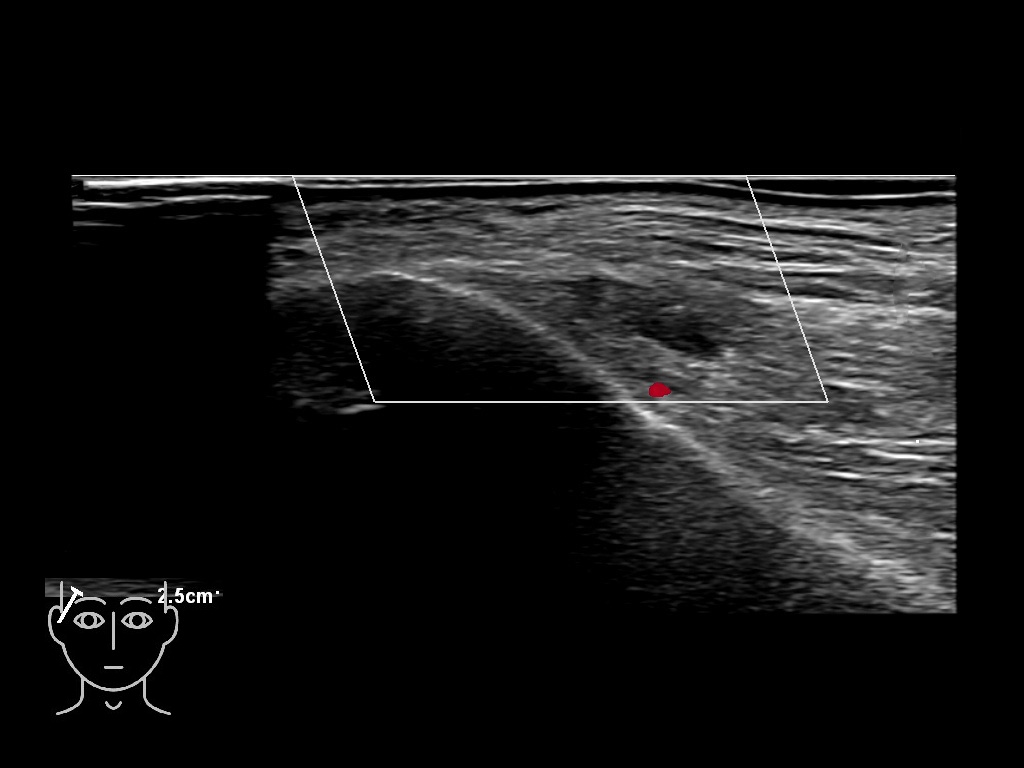

Draw in the image on the right where the fillers are located. To check if your answer is correct, please click on the secondary image.